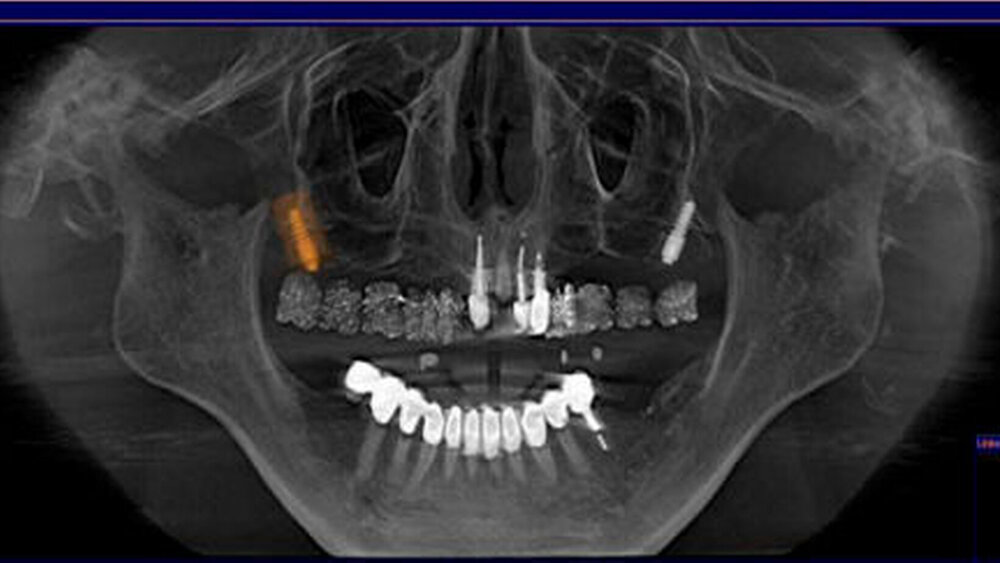

Sowohl die drei- als auch die zweidimensionalen Darstellungen der Hauptebenen ermöglichen eine einfache Orientierung; sie orientieren sich aber nicht direkt an der Anatomie. Einen wesentlichen Vorteil bietet dagegen die Darstellung von gekrümmten Oberflächen. Auf diese Weise können Ansichten aus den DVT-Volumendaten synthetisiert werden, die senkrecht auf der in der Transversalebene festgelegten Mittellinie durch den Kiefer stehen. So erhält man Ansichten, die dem Bildeindruck einer Panoramaschichtaufnahme (PSA) gleichen. Überlagerungsfreie Abschnitte lassen sich in jedem beliebigen Bereich des Aufnahmevolumens in einem separaten Befundungsfenster (dem sogenannten „inspection window“) bündeln, was eine exakte Diagnostik auch kleinster pathologischer Läsionen ohne störende Überlagerungsartefakte ermöglicht (Abbildung 4).

In den letzten Jahren hat die Bedeutung der 3D-Bildgebung für die präimplantologische Diagnostik zugenommen [Besimo et al., 1998; Krat, 1998]. Durch die DVT-Diagnostik steht eine Vermessungsoption zur metrischen Analyse zur Verfügung. Da die Darstellung der Schicht bereits metrisch kalibriert wurde, ist es im Gegensatz zur PSA nicht notwendig, eine Referenzkugel zur Kalibrierung zu verwenden. Mit der Messfunktion kann das Knochenangebot in horizontaler und vertikaler Dimension bestimmt werden. Ebenso ist es wichtig, bei der Planung die genaue Position der prothetischen Versorgung zu kennen. Hier kann entweder eine klassische Bohrschablone mit vom Zahntechniker eingebrachten Bohrhülsen oder eine Röntgenschablone zum Einsatz kommen. In der Röntgenschablone wird der prothetische Vorschlag des Zahntechnikers röntgenopak in bariumsulfathaltigem Kunststoff umgesetzt (Abbildung 7) [Zöller, 2007].